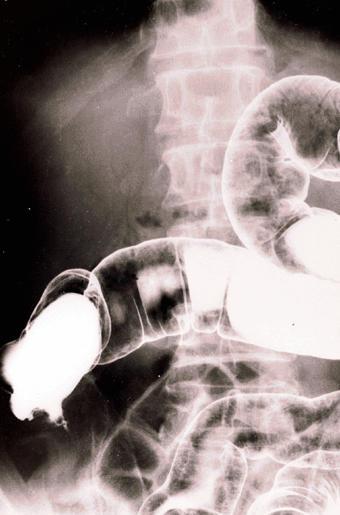

Tuberculosis of the ileocecal region which required an operation due to severe stenosis.

Inflammatory or ulcerative disease / lesions/tuberculosis

Large intestine(Colon)/Ilenocecal region

X-ray